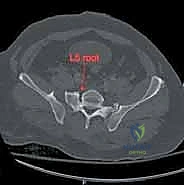

يمر عبر عظم العجز جذور الأعصاب العجزية التي تتحكم في وظائف حيوية مثل حركة الأطراف السفلية، التحكم في المثانة، ووظائف الأمعاء. أي انزياح عظمي في هذه المنطقة قد يؤدي إلى قطع أو انضغاط هذه الأعصاب، مما يسبب إعاقة دائمة إذا لم يتم تحريرها وتثبيت الكسر بدقة متناهية بواسطة خبير مثل الأستاذ الدكتور محمد هطيف.

3. التصوير المقطعي المحوسب (CT Scan): وهو المعيار الذهبي (Gold Standard) لتشخيص كسور الحوض والعجز. يقوم الدكتور هطيف باستخدام تقنية إعادة البناء ثلاثي الأبعاد (3D Reconstruction) لفهم هندسة الكسر بدقة متناهية قبل الدخول إلى غرفة العمليات.

يتم الاستعانة بجهاز الأشعة السينية المتحرك داخل غرفة العمليات (C-arm Fluoroscopy) للتأكد من وضعية المسامير بدقة المليمتر، لضمان عدم اختراقها للأعصاب أو الأوعية الدموية.